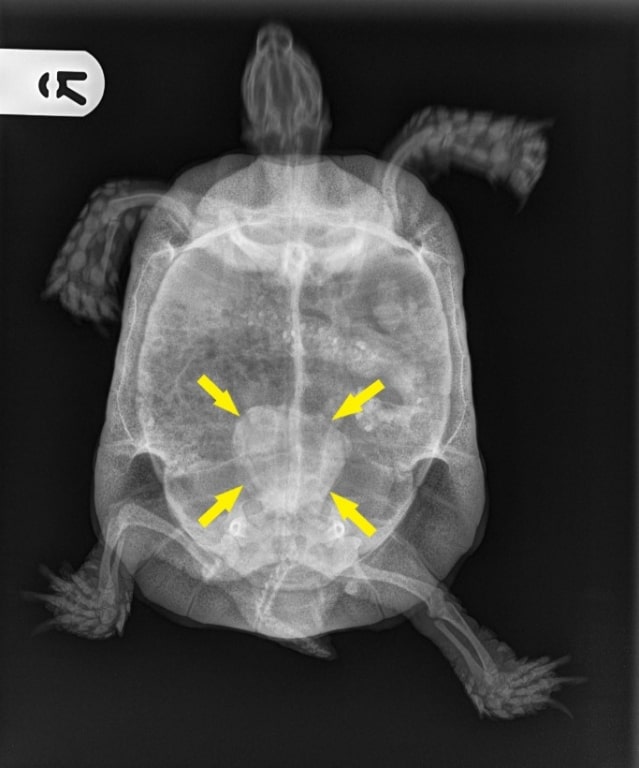

A shell-shocked tortoise with an eye-watering problem is now free from the acute pain and embarrassment of his troublesome condition.